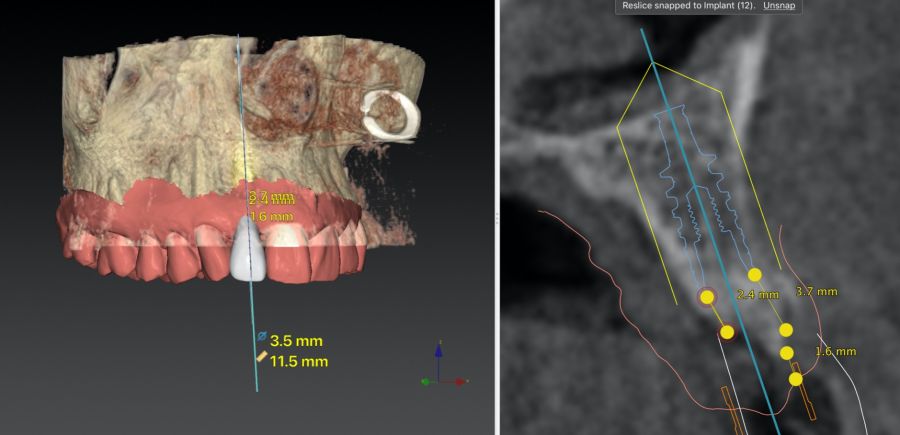

* Phase II: healing proceeded without complications. After 5 months from the alveolar preservation surgery, guided implant surgery was planned at position 1.2 (Figure 2). For this purpose, a DICOM file from cone beam computed tomography (CBCT) and an STL file obtained from scanning with an intraoral optical scanner were used. Using this information, a dental support surgical guide was fabricated (Figure 3). The surgical guide was anchored onto the teeth and guided the preparation of the implant bed and the placement of the implant. The guided surgery technique consisted of flap surgery, preparing and inserting the implant (3.5 x 11.5 mm) according to the standardised Nobel Active® guided surgery protocol (Nobel Biocare AB, Gothenburg, Sweden). Once implant 1.2 was placed,a gingival graft composed of epithelium and connective tissue from the palatal masticatory mucosa was obtained. Subsequently, the superficial epithelial layer of this graft was deepithelialised extraorally using a 15C scalpel blade in order to obtain a connective tissue graft from the underlying layer18.